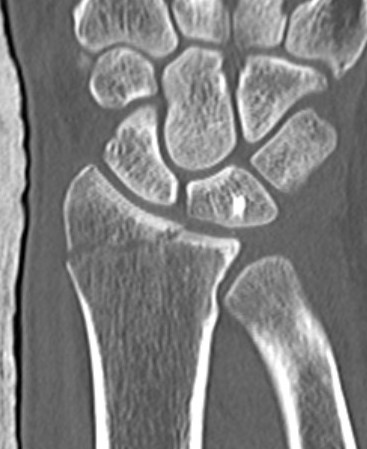

CT

Radial styloid + dorsal rim fractures